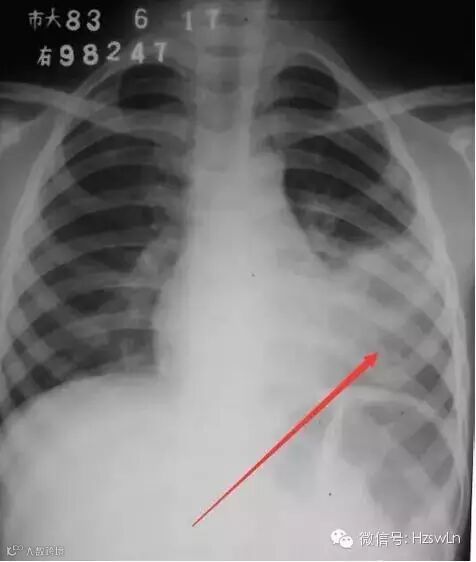

导读:基本情况:男性,12岁咳嗽、发热检查方法:胸部后前位片描述:左侧中下肺野中内带大片高密度影,密度不均,边缘模

基本情况:

男性,

12

岁咳嗽、发热

检查方法:

胸部后前位片

描述:

左侧中下肺野中内带大片高密度影,密度不均,边缘模糊。

初步诊断

:左下肺大叶性肺炎